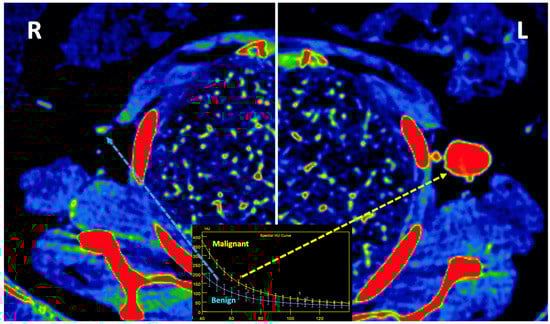

Figure 13. Prostate cancer (PCa) diagnosis. Incidental detection of a focal area of increased enhancement in the periphery of the prostate in contrast-enhanced CT may represent a clinically significant cancer (arrows) deserving of further workup. DECT imaging-based data such as a monoenergetic image at low energy values (e.g., 45 keV) and color-coded iodine map facilitate its detection. Note the difference between the spectral curve of the tumor (yellow curve, 1) and the normal parenchyma (blue curve, 2). Biopsy evidenced a prostate cancer having a Gleason score of 3 + 4. - LN characterization is challenging in oncologic imaging. Apart from morphologic criteria, different DECT parameters have been used, including iodine concentration, fat fraction, and similarity to the primary tumor [41,43]. Sauter et al. [44] evaluated standard values for of iodine concentration for healthy LNs in different anatomic areas that could be used to differentiate between healthy and pathological LNs. Recent studies have suggested lower iodine concentration in metastatic LNs compared to benign LNs [45]. However, the value of DECT imaging in differentiating malignant from non-malignant LNs seems to be limited and depends on the tumor type and technical features such as the protocols used for acquisition and contrast injection (Figure 14).

Figure 14. Lymph node (LN) imaging. Color-coded iodine maps of a left (L) axillary malignant LN (yellow arrow and yellow spectral curve, 1), which shows increased iodine uptake compared to a contralateral right (R) benign LN (blue arrow and blue spectral curve, 2). - Imaging of body composition is another growing application of DECT imaging that can be used to improve the evaluation of muscle tissue, visceral adipose tissue (VAT), and subcutaneous adipose tissue (SAT) compartments. SAT and VAT assessment is of special interest in diseases related to metabolic syndrome and critically ill patients [46]. Moreover, sarcopenia is associated with a poorer prognosis in cancer patients [47]. Measuring fat fraction of the skeletal muscle by DECT is a new approach for the determination of muscle quality, an important parameter for the diagnostic confirmation of sarcopenia [48]. In the case of bone mineral density analysis, DECT can provide a more detailed analysis when compared with dual X-ray absorptiometry [49] (Figure 15). Finally, DECT can also be a useful tool for evaluating silicone implants (Figure 16). Silicone contains the heavier element silicon (Z value = 14), whereas soft tissue predominantly comprises lighter elements, depicting the presence of silicone within the soft tissues in cases of silicone gel breast implant rupture and LN silicone spread [50].